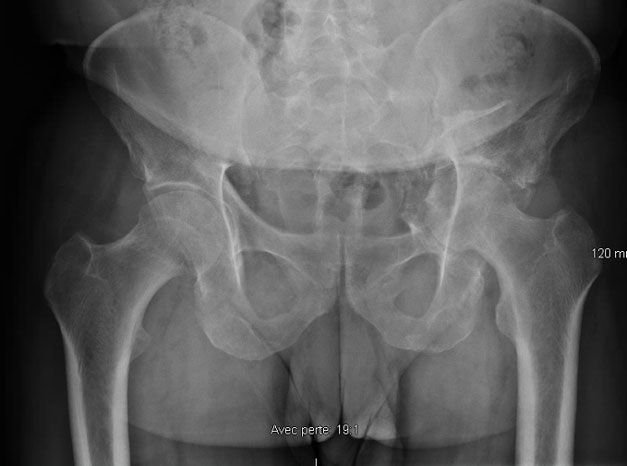

Images the day of the trauma

Sequela of an acetabular fracture: Images the day of the trauma

3 months after the trauma

Sequela of an acetabular fracture: 3 months after the trauma